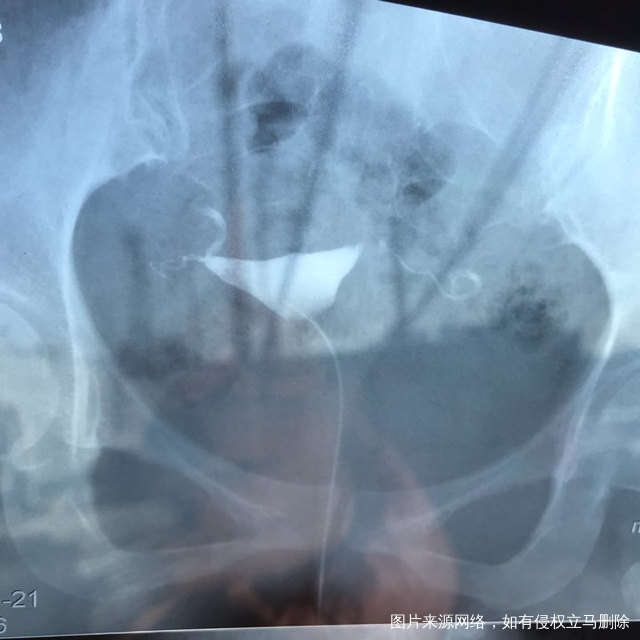

麻烦各位教授给我看看输卵管造影片子,谢谢了🙏